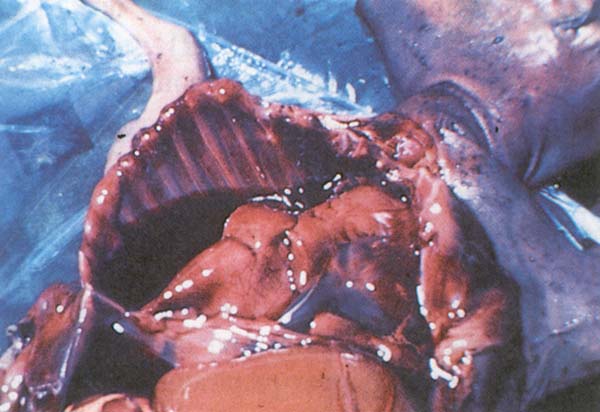

Otopsi bulguları :

- Midelerin (Şekil 161) ve bağırsakların akut hemorajik iltihabı

Şekil 161 : Nairobi koyun hastalığı. Midelerin akut hemorajik iltihabı.